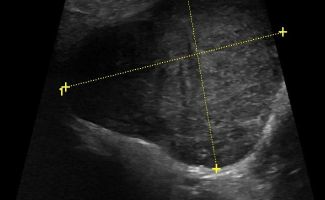

Το υψηλής ευκρίνειας Έγχρωμο Υπερηχογράφημα Σιελογόνων Αδένων με την τεχνική της Ελαστογραφικής Μελέτης μπορεί να διαγνώσει αξιόπιστα παθολογίες όπως;

- Διάταση των εκφορητικών πόρων και εντοπισμό λίθων στα πλαίσια σιελολιθίασης και σιελαδενίτιδας

- Αυτοάνοσα νοσήματα, όπως σύνδρομo Sjogren

- Εστιακές βλάβες, όπως όγκοι (πλειόμορφο αδένωμα, όγκος Warthin, λέμφωμα)

Η αξιοπιστία του Υπερηχογραφήματος στη διάγνωση παθολογίας των Σιελογόνων Αδένων έχει καθιερωθεί τα τελευταία χρόνια και εξασφαλίζεται με τη χρήση Υπερηχογράφων τελευταίας γενιάς με ειδικούς υψίσυχνους ηχοβολείς και με την εξοικείωση και εμπειρία του εξεταστή-ιατρού με την ηχοανατομία και παθολογία των Σιελογόνων Αδένων και της περιοχής κεφαλής – τραχήλου.